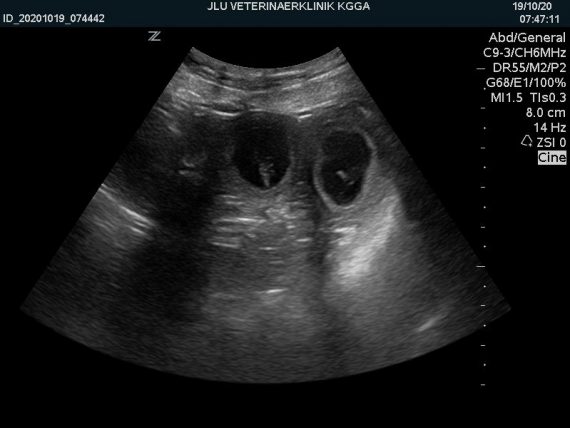

Tolle Nachrichten aus dem Haus ASKAARDIA Wie auf den Ultraschall-Bildern dokumentiert: Die Paarung unserer ASKANTI mit einem der besten Rüden der Welt LORD from the Dogsfarm hat wieder geklappt. ASKANTI hat aufgenommen und es ist Einiges an Nachwuchs zu erwarten! Wir freuen uns mit allen, die uns schon vorab zu dieser Paarung gratuliert haben, jetzt…